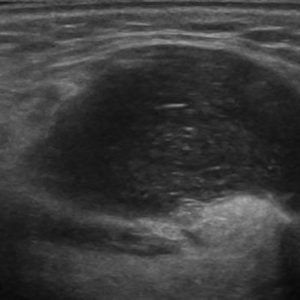

U tuyến nước bọt

Lượt xem: 146» 19-01-2021 -

U tuyến nước bọt

Lượt xem: 160» 19-01-2021 -